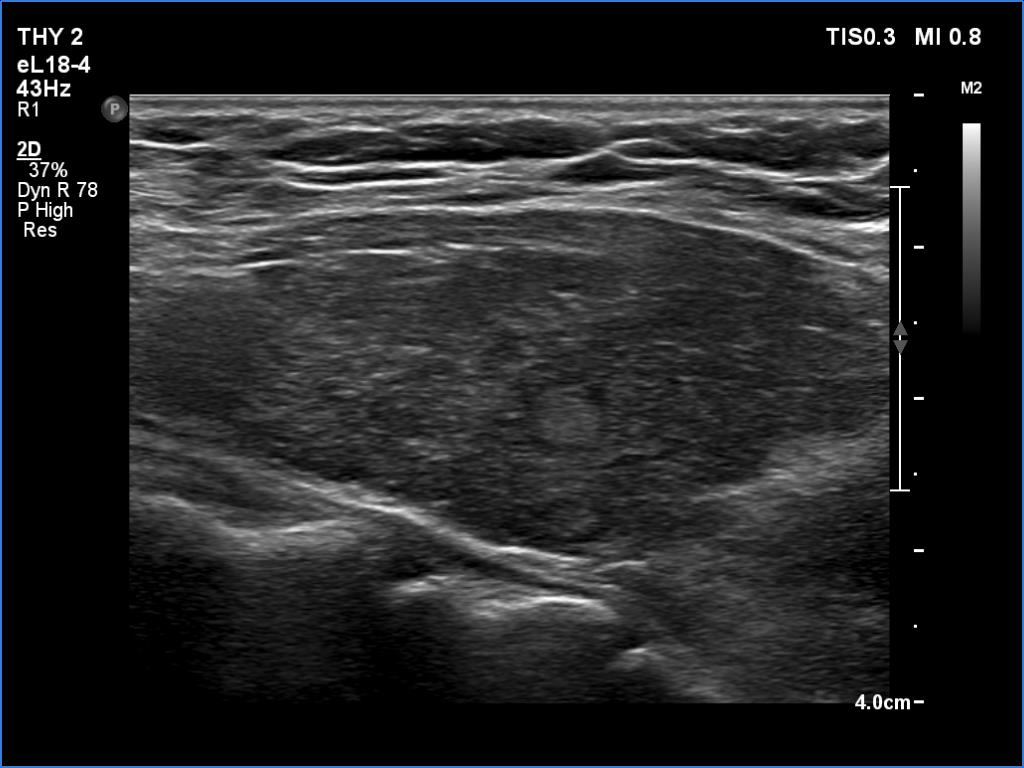

Before the surgery (first row of images):

Clinical data: A 50-year-old woman has been treated for Graves' disease for three years. The hyperthyroidism has recurred four times during this period, and this recurrence were characterized by a > 55 pM/L FT4-level.

Palpation: Both lobes were a enlarged and not firm.

Laboratory tests: TSH 0.01 mIU/L, FT4 22.3 pM/L, FT3 11.4 pM/L on daily 10 mg methimazole.

Ultrasonography. The thyroid was moderately hypoechoic and inhomogeneous. There was small echonormal discrete lesion in the left lobe. The vascularity was a bit increased.

Suggestion: to increase the dose of methimazole to daily 21 mg. After restoration of thyroid hormones, surgery. (The patient's mother was sent for radioiodine treatment for Graves' disease 15 years ago. After treatment, a level of TAO developed that significantly and permanently impaired quality of life.)

Total thyroidectomy was performed.  Histopathology disclosed diffuse goiter corresponding to Graves' disease. A solitary, two-millimeter papillary cancer was found in the right lobe.